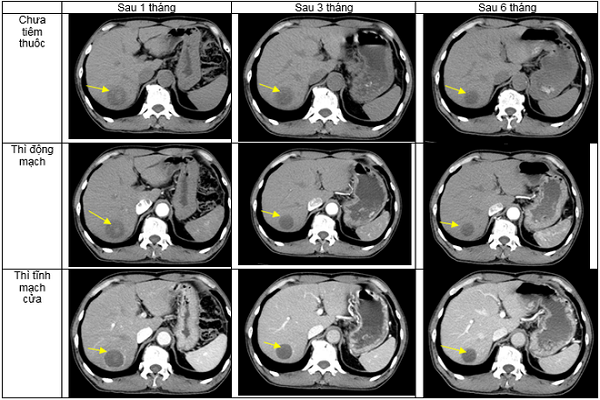

Bệnh nhân được đánh giá đáp ứng điều trị sau một tháng, sau 3 tháng và sau 6 tháng. Sau điều trị, triệu chứng cơ năng của bệnh nhân cải thiện nhiều, bệnh nhân ăn ngủ tốt, tăng 3kg, không còn đau tức hạ sườn phải.

![]() |